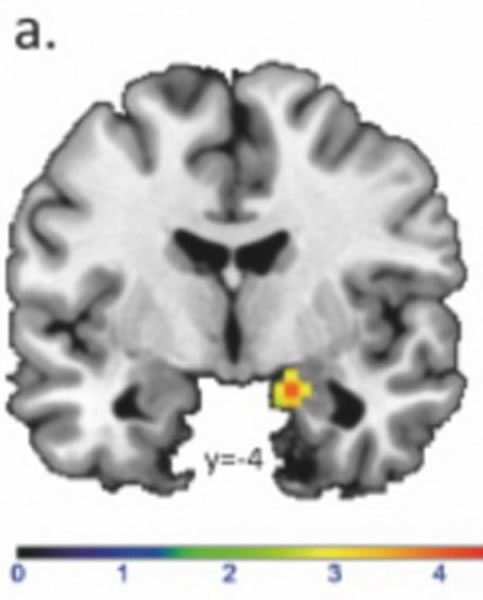

德国波鸿市LWL大学附属医院的研究人员称,我们招募了22位男性测试者,让他们注视观看36对眼睛图片,其中18对眼睛图片是女性,18对眼睛图片是男性。功能性磁共振扫描成像结果表明,事实上男性很难解析掌握女性的情绪和思维,男性志愿者在解读女性情绪时需要的时间更长,并且正确率很低,其难度是感受男性情绪变化的两倍。当志愿者注视男性眼睛图片时,他们大脑的杏仁体与情绪和害怕相关联的区域活动性更强,当注视女性眼睛图片时,大脑中与情绪和行为相关区域更为活跃。

核磁共振扫描图像显示,男性识别分析女性情绪变化的能力较差,其难度是感受男性情绪变化的两倍